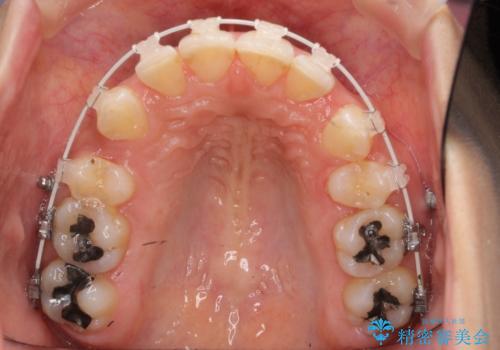

Eラインを整える治療 前歯を引っ込めます

- 矯正装置

- 審美装置

- 治療計画

- 前歯を下げたいと来院。

初めは、上だけ抜歯しましたが、もう少し口元を下げたいとのことで追加で下顎を抜歯しました。

年齢の割に歯が動きにくかったこともあり、また、追加で抜歯して結果として時間がかかってしまいました。口元が大きく下がり、結果には満足していただけました。